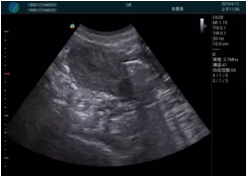

便攜超聲引導(dǎo)下人流術(shù)

病例一:

清晰顯示孕囊,通過軟件包計(jì)算孕齡7w+6d

M20實(shí)時引導(dǎo),術(shù)中清晰顯示孕囊被破壞和抽吸針的過程,清晰顯示吸引針

抽吸結(jié)束后縱切子宮,孕囊已被完全抽吸,未見明顯殘留

橫切子宮,發(fā)現(xiàn)右側(cè)宮腔靠近宮角處有少許脫模樣殘留

M20引導(dǎo)下,抽吸針找到右側(cè)宮角處再次清掃

二次抽吸后再次進(jìn)行超聲檢查,宮腔未見殘留,宮腔線清晰顯示

超聲引導(dǎo)下可視化人流是技術(shù)安全性的保障,一般對人流術(shù)設(shè)備預(yù)算不高,M20具備婦產(chǎn)科軟件包,且穿透力圖像質(zhì)量好,既滿足人流引導(dǎo)需要,也可用于床旁超聲的需求。